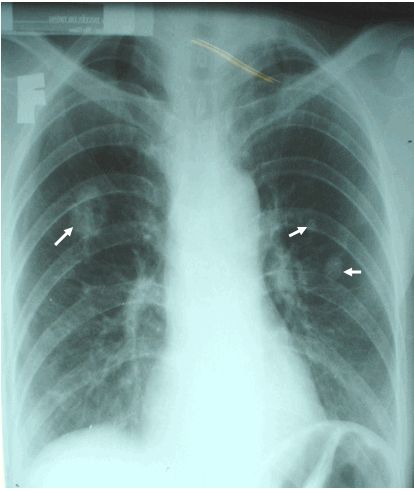

Bệnh bụi phổi (Silicosis) trên phim x quang

Bệnh bụi phổi là bất kỳ của nhiều bệnh phổi do hít phải nhiều bụi hữu cơ hoặc vô cơ hay hóa chất kích thích, thường trong một khoảng thời gian dài. Các loại và mức độ nghiêm trọng của bệnh phụ thuộc vào thành phần của bụi; số lượng nhỏ của một số chất, đặc biệt là silica và amiang, tạo ra phản ứng nghiêm trọng.

Thông thường, các triệu chứng sớm của bệnh bụi phổi nhẹ bao gồm đau thắt ngực, khó thở và ho, tiến triển đến suy hô hấp nghiêm trọng hơn, mãn tính viêm phế quản và khí phế thũng trong các trường hợp nghiêm trọng nhất. Bụi hít thu thập trong các phế nang hay túi khí, phổi, gây ra phản ứng viêm có thể chuyển đổi mô phổi bình thường đến mô sẹo xơ và do đó làm giảm độ đàn hồi của phổi. Nếu nhiều mô sẹo hình thành, chức năng phổi bị suy giảm nghiêm trọng, và các triệu chứng lâm sàng của bệnh bụi phổi được thể hiện.